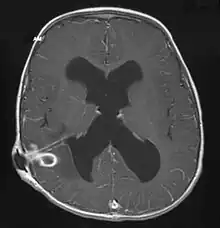

| Brain abscess in a person with a CSF shunt. The abscess is the darker gray region in the lower left of the image (corresponding to the right parietal lobe). The lateral ventricles are visible in black in the center of the brain, adjacent to the abscess.[1] | |

Brain abscess (or cerebral abscess) is an abscess within the brain tissue caused by inflammation and collection of infected material coming from local (ear infection, dental abscess, infection of paranasal sinuses, infection of the mastoid air cells of the temporal bone, epidural abscess) or remote (lung, heart, kidney etc.) infectious sources. The infection may also be introduced through a skull fracture following a head trauma or surgical procedures. Brain abscess is usually associated with congenital heart disease in young children. It may occur at any age but is most frequent in the third decade of life.